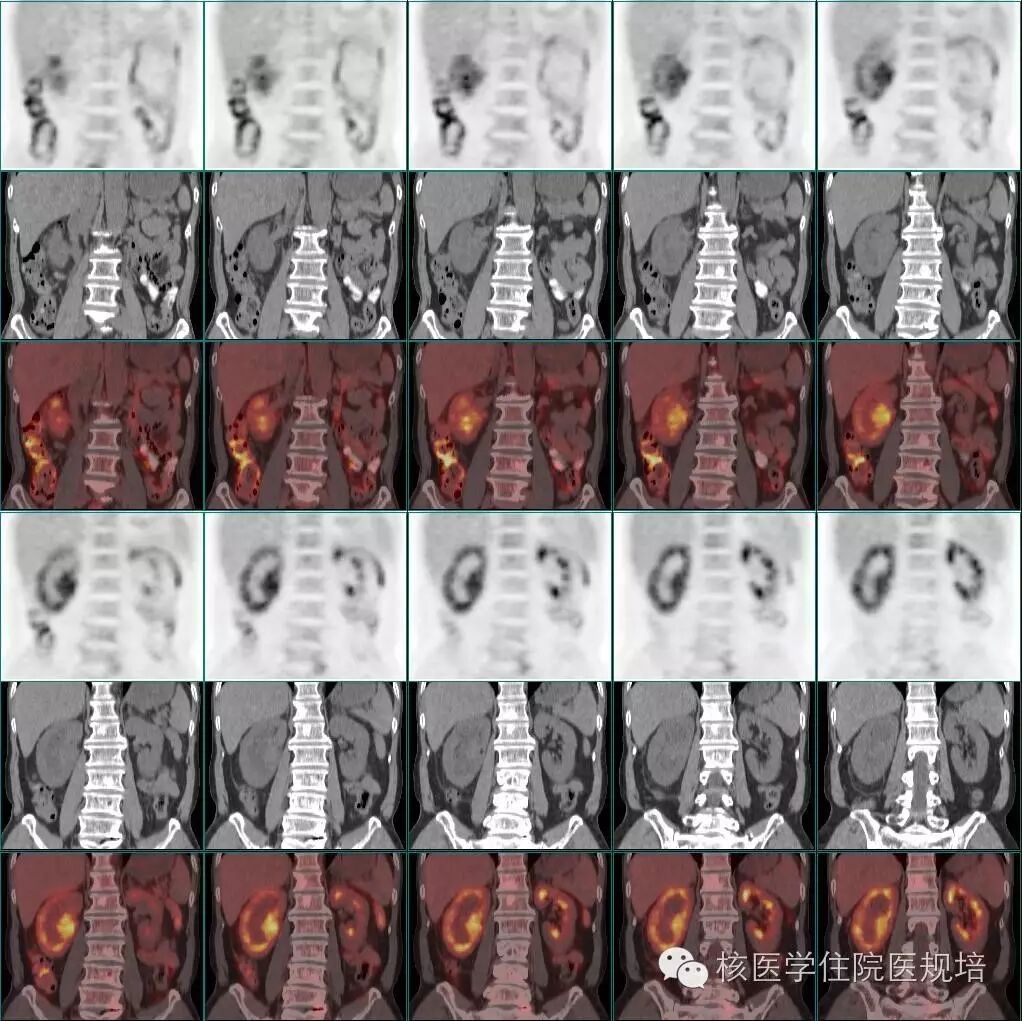

整体观察见MIP图(图3)。主要阳性发现包括:左心房、主动脉及肺动脉主干周围可见环形、弥漫性FDG摄取(SUVmax 3.8),但相应部位平扫CT未见明确异常结构改变(图4);右肾盂扩张,内见形态不规整FDG摄取增高软组织密度肿物影(SUVmax 4.9),边缘毛糙,范围约3.6 cm×2.9 cm×3.0 cm,并包绕上段输尿管,同时见右肾盂积水(图5);四肢长骨FDG摄取对称性增高(SUVmax 3.2),自关节端向骨干伸,相应部位CT见不规则骨质硬化,其中右股骨内侧髁可见溶骨性骨质破坏(图6);脊柱及骨盆亦可见多发性质类似的骨病变(图7、8)。

图6. 四肢长骨对称性FDG摄取增高伴不规则骨质硬化及右股骨内侧髁溶骨性骨质破坏

图7. 脊柱多发骨病变

图8. 骨盆多发骨病变